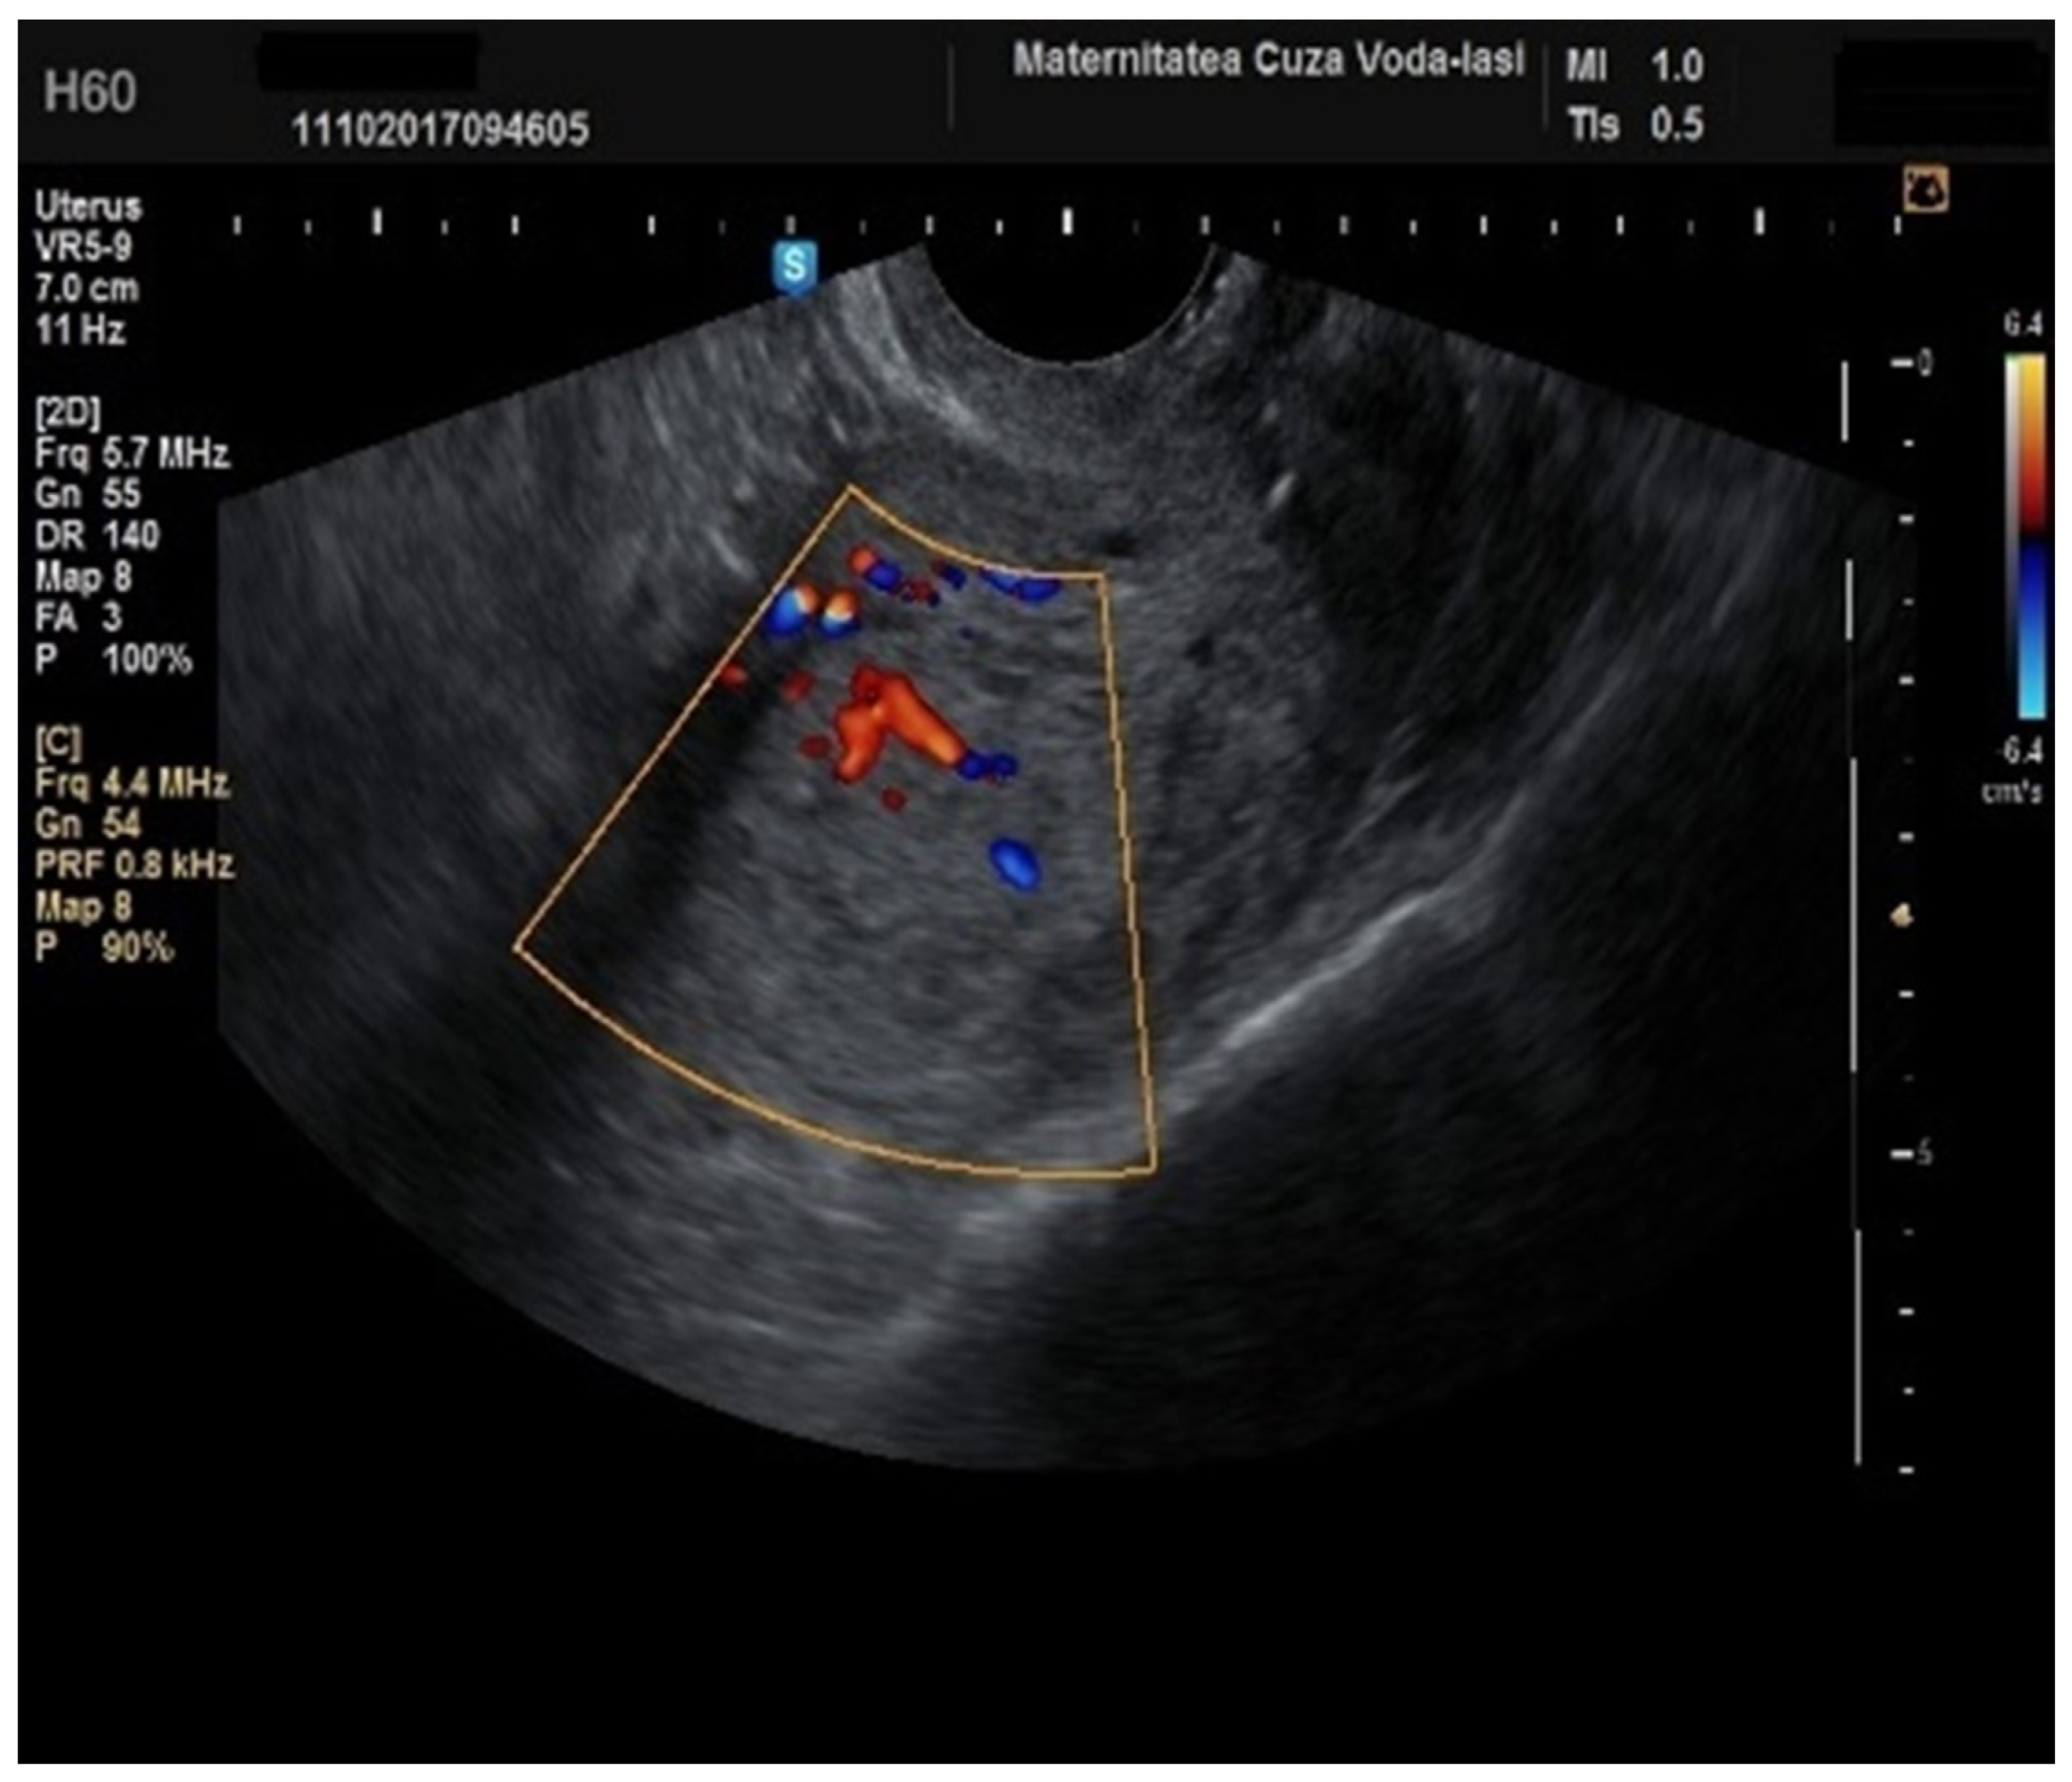

Furthermore, color Doppler imaging proved valuable in more accurately determining myometrial invasion. The predominant feature of blood vessels in endometrial cancer was the presence of scattered vessels (Figure 10), which demonstrated a sensitivity of 50% (95% CI: 0.2152 to 0.7848) and a specificity of 94.74% (95% CI: 0.8563 to 0.9819). Additional vascular aspects indicative of endometrial cancer were the presence of vessels with various branches (Figure 11) and color splashes (Figure 12).

Figure 11. Color Doppler imaging for assessing endometrial invasion in endometrial cancer: presence of vessels with multiple branches.